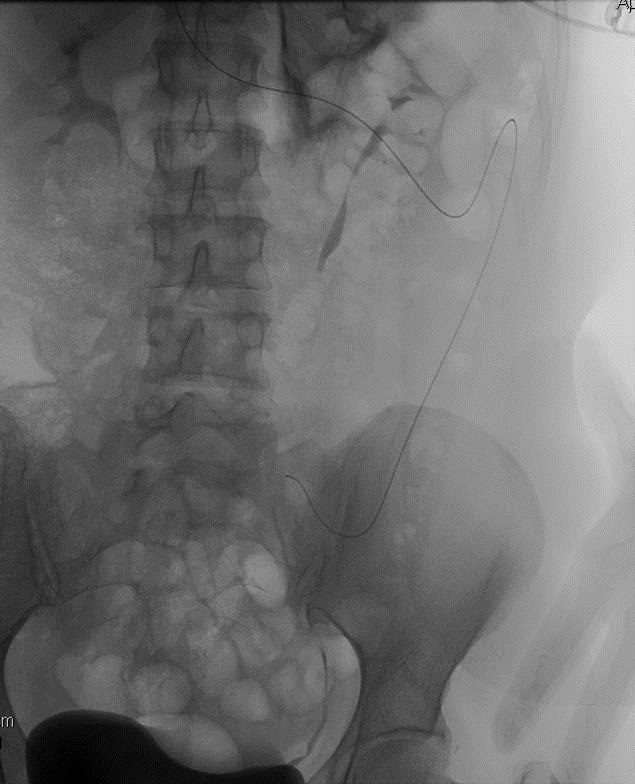

静脉源性肾脏症状(历史上称为为Nutcracker syndrome/ Nutcracker phenomenon NCS/NCP)、、【K Ananthan 2017】 ![]() 胡桃夹现象=NCP 被定义为一种解剖状况,其特征是外源性血管压迫左肾静脉,导致左肾静脉流出受阻 可以没症状? 胡桃夹子综合征= NCS 定义应保留在有典型相关临床症状的情况下

胡桃夹现象(Nutcracker phenomenon)指左肾静脉回流入下腔静脉过程中在穿经由腹主动脉和肠系膜上动脉形成的夹角或腹主动脉与脊柱之间的间隙内受到挤压,常伴有左肾静脉血流速度的下降、受压处远端静脉的扩张。当胡桃夹现象引起血尿、蛋白尿和左腰腹痛等一系列临床症状时,称为胡桃夹综合征(Nutcracker syndrome)或左肾静脉压迫综合症(Left renal vein entrapment syndrome)。胡桃夹综合征年轻女性疾病处于早期,人到中年疾病进入晚期,或后期。

Definitions: • Anterior Variant: Compression of the left renal vein (LRV) between the aorta and the superior mesenteric artery (SMA)

• Phenomenon- compression left renal vein between abdominal aorta and SMA

前胡桃夹现象